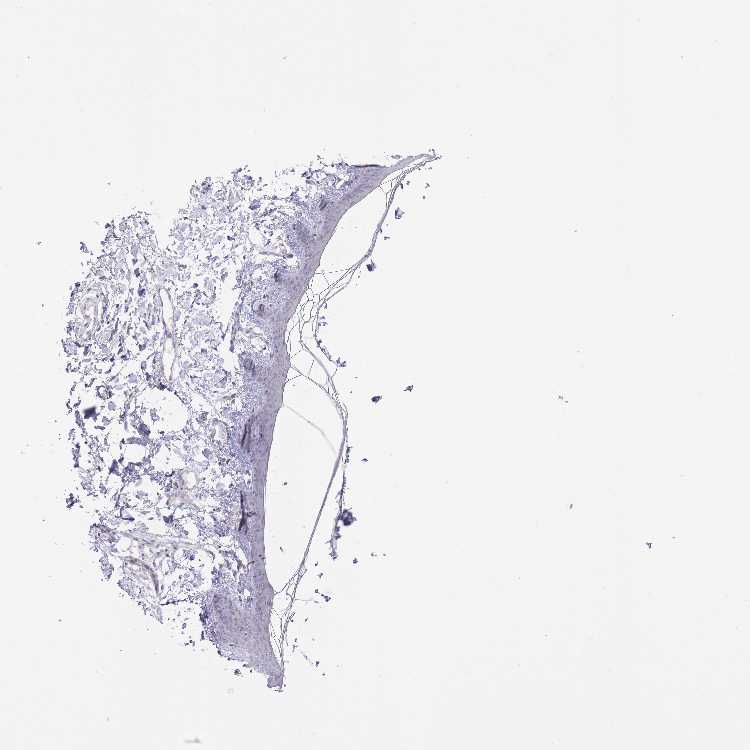

SKIN 1 - Antibody stainingi

Antibody staining in the annotated cell types in the current human tissue is reported as not detected, low, medium, or high, based on conventional immunohistochemistry profiling in selected tissues. This score is based on the combination of the staining intensity and fraction of stained cells.

Each image is clickable and will lead to virtual microscopy that enables deeper exploration of all samples and also displays staining intensity scores, fraction scores and subcellular localization as well as patient and tissue information for each sample.

Antibody HPA045712

Langerhans Medium

Fibroblasts Medium

Keratinocytes Medium

Melanocytes Not detected

SKIN 2 - Antibody stainingi

Epidermal cells Medium